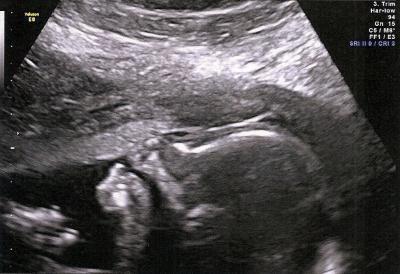

Hallo ihr Lieben, nachdem ich den Termin letzte Woche ja absagen musste, hatte ich nun endlich heute mein Organscreening. Ich bin so froh, dass alles ok ist. Die Ärztin war auch super. Sie war total interessiert und hat uns alles erklärt. Leider hat sie keinen 3D-Schall gemacht, aber egal, die Gesundheit unserer Kleinen ist mir viel wichtiger. Das Outing (Mädchen) wurde auch nochmal eindeutig bestätigt. Unsere Maus saß nämlich im Schneidersitz da, sehr zeigefreudig. :-) Momentan ist sie in Beckenendlage, aber sie hat ja noch genügend Platz, um sich zu drehen. Morgen Abend schauen wir uns nochmal die Klinik an, in der ich schon meinen Sohn entbunden habe und auch wieder entbinden werde. Allerdings gibt es jetzt einen anderen (meiner Meinung nach noch besseren) Chefarzt. Bin mal gespannt. LG und einen schönen Abend euch allen!

Bild zu Noch ein Organscreening-Bericht - Forum für April - Mamis